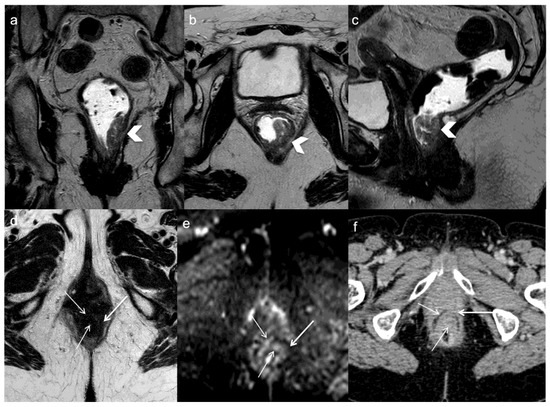

- Shin, S.S.; Jeong, Y.Y.; Kang, H.K. CT Findings of Locoregional Recurrence after Curative Resection of Colorectal Cancer. J. Korean Radiol. Soc. 2006, 55, 387. [Google Scholar] [CrossRef]

- Pema, P.J.; Bennett, W.F.; Bova, J.G.; Warman, P. CT vs. MRI in diagnosis of recurrent rectosigmoid carcinoma. J. Comput. Assist. Tomogr. 1994, 18, 256–261. [Google Scholar] [CrossRef]

- Tan, P.L.; Chan, C.L.H.; Moore, N.R. Radiological appearances in the pelvis following rectal cancer surgery. Clin. Radiol. 2005, 60, 846–855. [Google Scholar] [CrossRef]